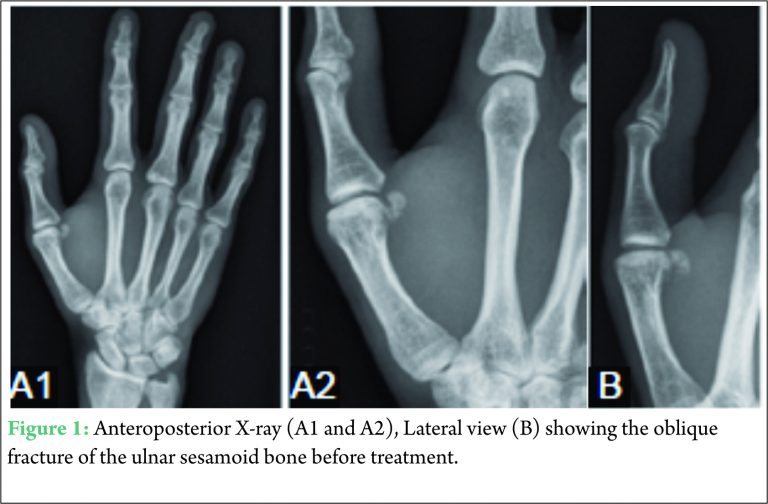

A 35-year-old male patient presented at the emergency department complaining of persisting pain and functio laesa of his right thumb since the day before. During a fall with his mountain bike, our patient hyperabducted and – extended his right thumb violently. The patient described a (sub) luxation of the MCPJ of the pollex which he reduced himself, no analgesics or ice application were applied by the patient. Clinical examination at the emergency department showed a swollen MCP-I joint (MCPJ) with ecchymosis at the base of the thumb. Painful palpation was noted at the MCPJ, no pain could be provoked at the interphalangeal joint or after pressure on the scaphoid bone. Passive and active movements (abduction, adduction, opposition, flexion, and extension) of the thumb were normal. No crepitations were objectivized. Peripheral movements, blood circulation, and sensitivity were intact. An anteroposterior X-ray demonstrated an oblique fracture of the ulnar sesamoid of the caput metacarpalis of the right thumb (Fig. 1). A Stener lesion or partial rupture of the UCL was excluded after an ultrasound examination.